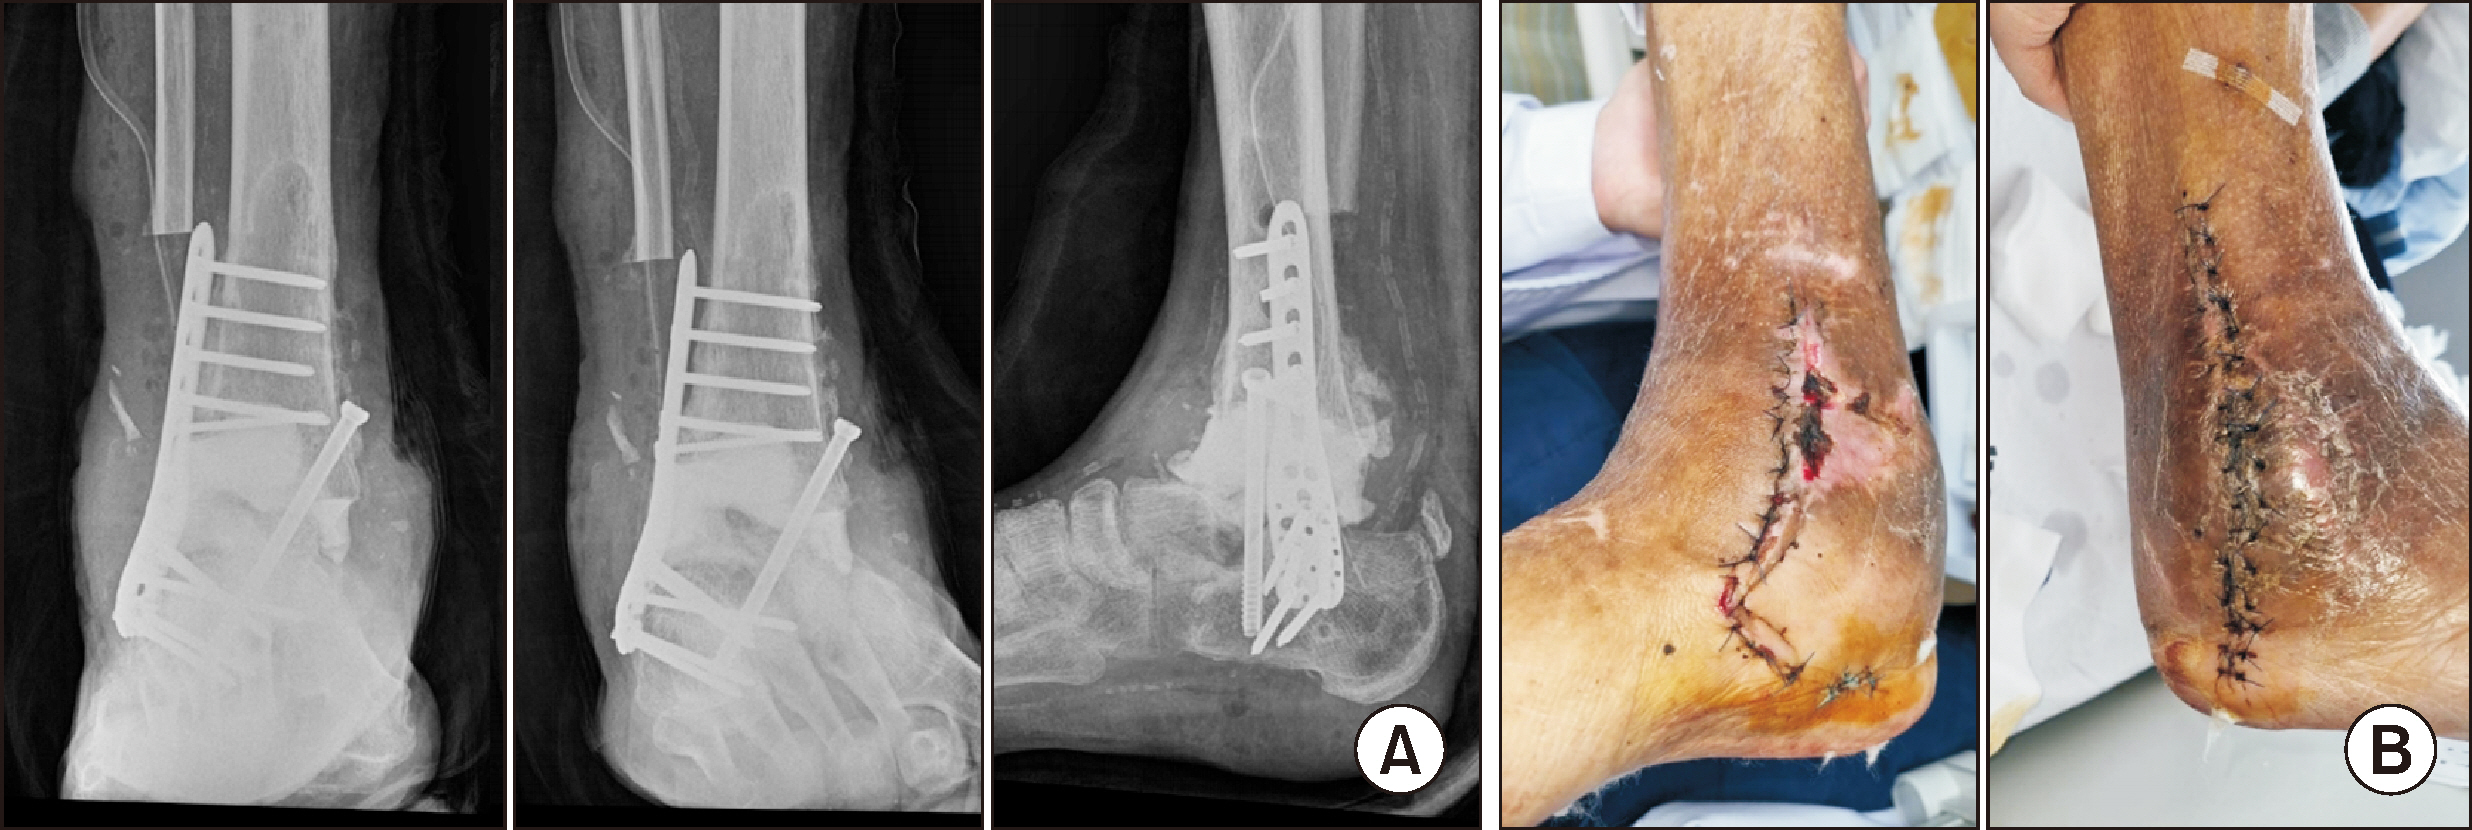

Comprehensive Management of Presumed Underlying Charcot Arthropathy with a Subsequent Traumatic Ankle Fracture in a Patient with Diabetes Mellitus, End-Stage Renal Disease: A Case Report

Charcot neuroarthropathy (CN), also known as Charcot arthropathy, is a complex, progressive disorder primarily affecting the foot and ankle. This case report describes a multifaceted management strategy for a 54-year-old male with diabetes mellitus, end-stage renal disease, and presumed underlying Charcot arthropathy who experienced a traumatic ankle fracture. The initial surgical plans were delayed because of systemic infection indicators, including elevated C-reactive protein levels and high fever. The patient underwent multiple surgical interventions and faced challenges, including metal failure, implant-associated infection, and tibiotalar joint dislocation. A multidisciplinary approach involving orthopedic surgeons, nephrologists, and endocrinologists was crucial for managing the case effectively. In particular, the patient declined a below-knee amputation and opted for comprehensive surgical intervention, resulting in improved functionality at the latest follow-up. This case highlights the complexities of managing CN in patients with multiple comorbidities and emphasizes the need for a nuanced, patient-centered approach.